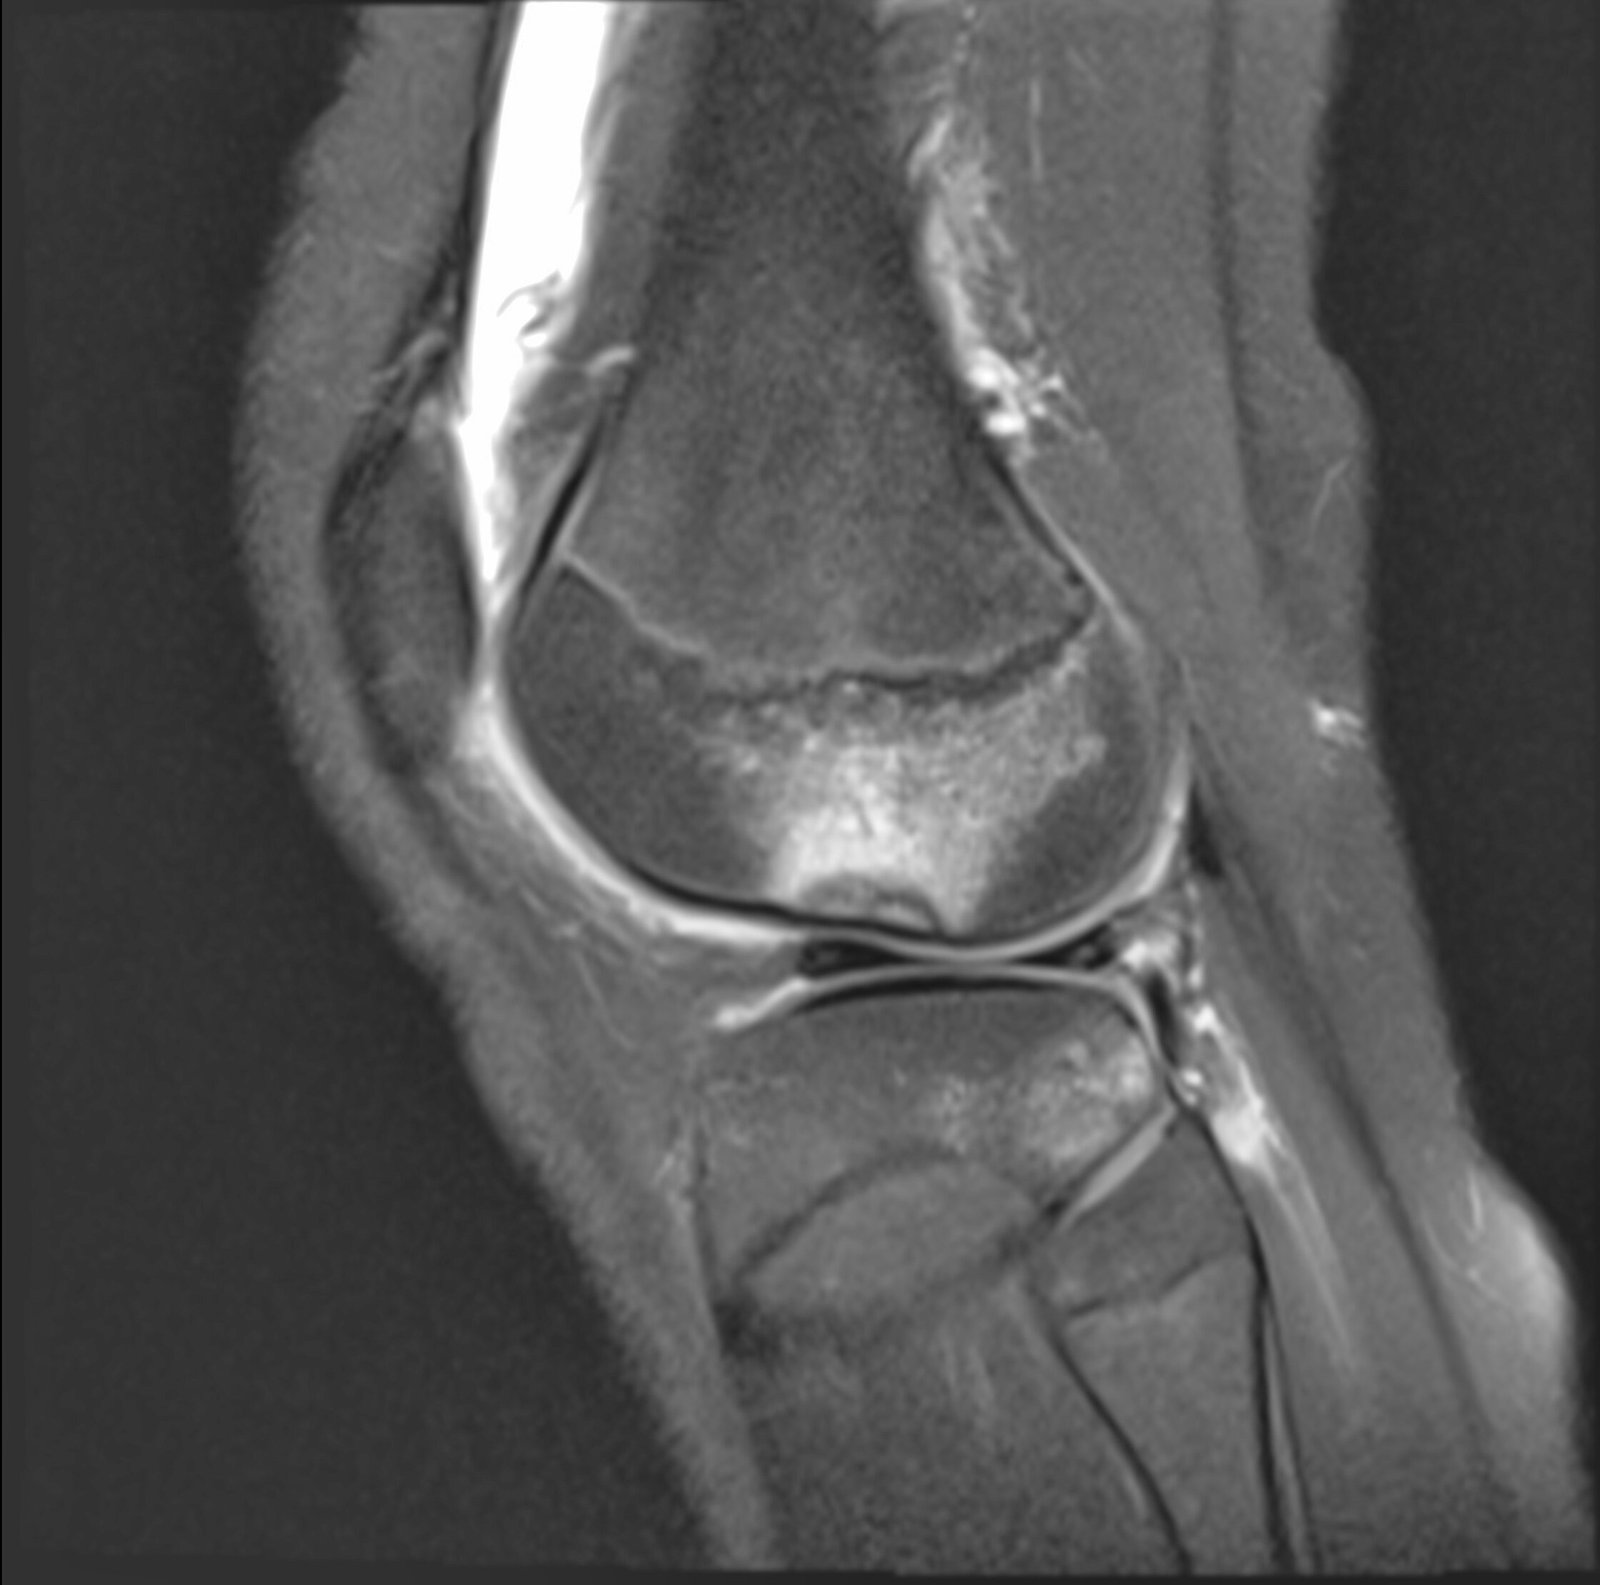

A lo largo de nuestra trayectoria, hemos sido pioneros en técnicas avanzadas de imagen cardíaca y procedimientos intervencionistas que evitan cirugías innecesarias . Hoy, con la incorporación de la resonancia magnética de 1.5 Teslas, reafirmamos nuestro compromiso de ser el aliado principal de los médicos y pacientes en Loja .